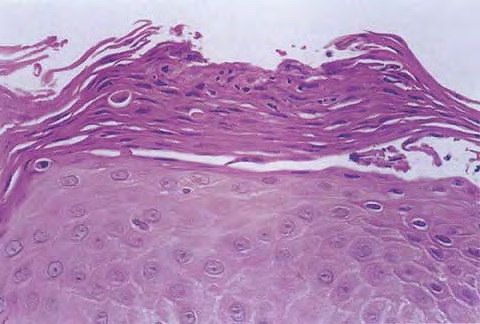

Histopathology. The histopathologic features are a combination of those observed in psoriasis and spongiotic dermatitis. Mild cases may exhibit only slight subacute spongiotic dermatitis. The stratum corneum contains focal parakeratosis, with a predilection for the follicular ostia, a finding known as shoulder parakeratosis . Occasional pyknotic neutrophils are present within parakeratotic foci {neutrophilic parakeratosis}, sometimes with fluid {neutrophilic crust}. There is moderate acanthosis with regular elongation of the rete ridges, mild spongiosis, and focal exocytosis of lymphocytes. The dermis contains a sparse mononuclear cell infiltrate. In HIV-infected patients, the epidermis contains apoptotic keratinocytes, and the dermal infiltrate usually contains plasma cells. |